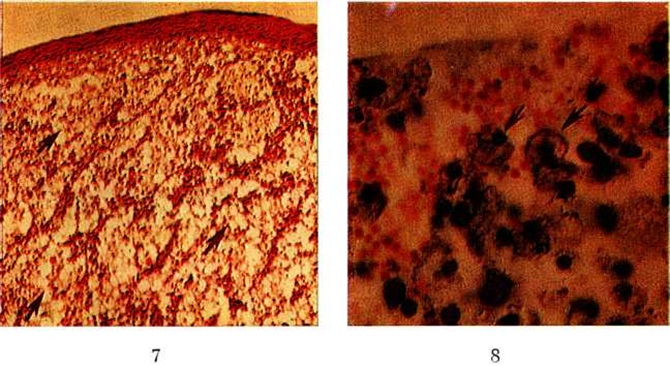

В клетках Микулича, а иногда и вне их при применении специальных окрасок выявляется палочка Волковича —Фриша (цветной рисунок 8). Эозинофильные и нейтрофильные лейкоциты (гранулоциты) присутствуют в относительно небольшом количестве. Характерно наличие в специфической грануляционной ткани так называемый русселевских телец, известных также как гиалиновые тельца Пеллиццари и Корниля. Большинство исследователей связывают происхождение клеток Микулича с присутствием в моноцитарных макрофагах палочек Волковича—Фриша. С помощью электронной микроскопии (смотри полный свод знаний) в цитоплазме фагосом клеток Микулича обнаружены палочки Волковича—Фриша как интактные, так и находящиеся на разных стадиях переваривания. Наличие пенистой цитоплазмы клетки Микулича объясняют накоплением в фагосомах непереваренных бактериальных гликозаминогликанов, которые, повышая осмотическое давление, способствуют вакуолизации и разрыву фагосом. Эпителий над склеромными грануляциями в различной степени инфильтрирован нейтрофильными лейкоцитами. В клетках эпителия отмечаются признаки вакуольной дистрофии (смотри полный свод знаний), сосочковый слой кожи сглажен, подвергается атрофии, которая наблюдается также в сальных и потовых железах, фолликулах волос. Цилиндрический мерцательный эпителий слизистых оболочек замещается многослойным плоским, иногда с патологический ороговением типа гиперкератоза (смотри полный свод знаний: Кератозы) и паракератоза (смотри полный свод знаний), образует акантотические погружения в специфическую грануляционную ткань, иногда с атипическими реактивными разрастаниями. Над крупными бугристыми узлами может наблюдаться истончение эпителиального покрова до 2—3 рядов уплощённых клеток. Существенное место в развитии склеромных поражений занимают явления склероза (смотри полный свод знаний), обусловленного ростом и созреванием специфической грануляционной ткани. Образование коллагеновых волокон в виде пучков начинается в глубоких отделах склеромных грануляций и идёт по направлению к поверхности. При этом грануляционная ткань разделяется на отдельные островки, охваченные грубыми, нередко гиалинизированными пучками коллагена (смотри полный свод знаний). Наряду с этим отмечается новообразование эластических волокон. Исчезновение специфической грануляционной ткани при лечении стрептомицином также связано с усилением склерозирования, при этом в первую очередь наблюдается уменьшение количества, а затем исчезновение в грануляционной ткани клеток Микулича. При длительном течении Склерома специфические морфологический изменения иногда наблюдаются в регионарных лимфатических, узлах. Во внутренних органах каких-либо специфических проявлений склеромы не обнаружено. Клиническая картина. Склерома протекает годами и десятилетиями. Инкубационный период длится несколько лет. Большинство больных заболевают в возрасте 15—20 лет, встречаются случаи заболевания и в детском возрасте. В течении Склерома выделяют три периода: доклинический, в котором выявляются положительные результаты серологический исследований, но ещё отсутствуют клинические, проявления; клинический, характеризующийся явными клинические, проявлениями и положительными серологический реакциями; резидуальный, в котором наблюдаются лишь остаточные явления (рубцы, атрофия слизистых оболочек). Клинически Склерома протекает в двух формах — продуктивной и дистрофической, которые в ряде случаев сочетаются. Для продуктивной формы характерно появление гранулематозных изменений, увеличивающихся либо экзофитно в виде пышных, иногда опухолевидных образований, либо эндофитно — под слизистой оболочкой, в виде плотных инфильтратов. Гранулематозные разрастания не имеют склонности к распаду и со временем замещаются плотным рубцом (смотри полный свод знаний). Склеромные продуктивные изменения в области носа чаще обнаруживают в области порога полости носа, который кольцеобразно сужен, а также распространяются на верхнюю губу и крылья носа (рисунок 1). По носослёзному протоку процесс распространяется на область слёзных точек (рисунок 2); в единичных случаях поражается глазница. Инфильтраты, расположенные в области хоан, концентрически суживают их просвет, распространяясь на носоглотку, воронкообразно суживают её или образуют кулисовидные тяжи. Вовлечённое в процесс мягкое небо подтягивается вверх, нёбный язычок отгибается и припаивается к верхней поверхности мягкого неба. Иногда склеромные инфильтраты переходят на нёбно-язычные и нёбно-глоточные дужки, миндалины, язык, концентрически суживая зев, изредка обнаруживаются в преддверии рта. В гортани гранулематозные изменения встречаются в любом её участке; наиболее типичным является образование валикообразных инфильтратов в подголосовой полости. В трахее и бронхах инфильтраты чаще всего находятся на киле трахеи, но бывают и на других участках.